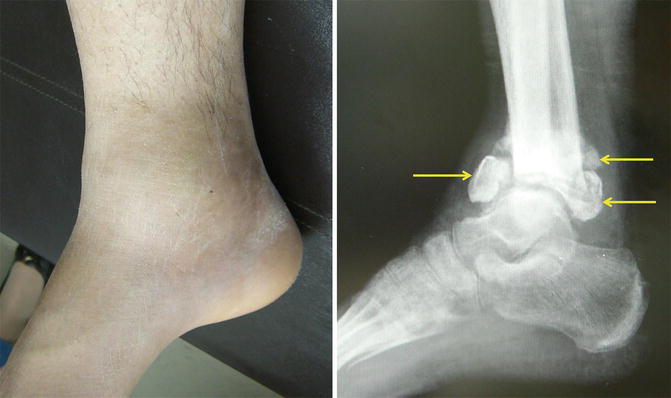

Fig. 6.6

Limited motion of the ankle joint by calcification of the joint capsule (arrows)